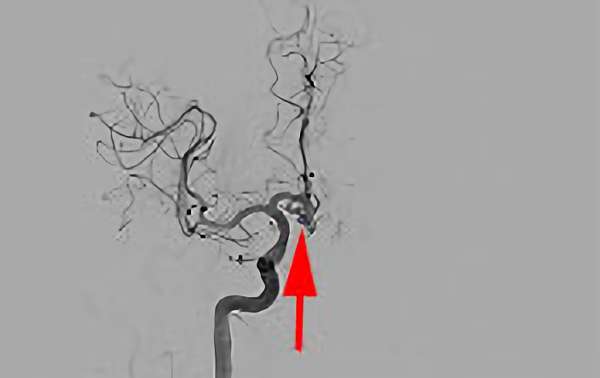

No.1600 手術中